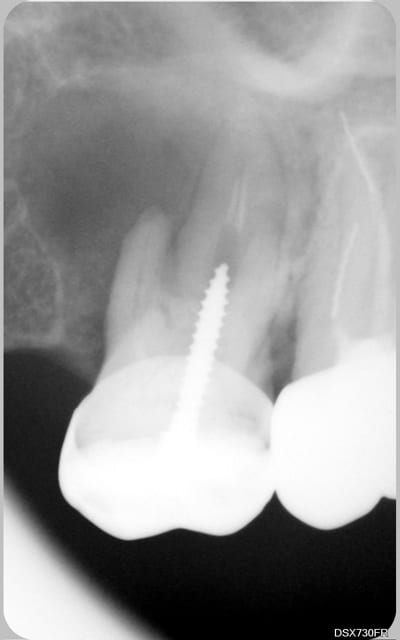

tu veux des images...en voilà 2...avant traitement et 6 mois plus tard...

C'est un beau début de cicatrisation.

Un début de guérison c'est léger pour un fil lu 1463 fois.